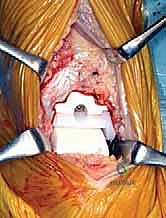

TECH FIG 3 • Osteotomy of tibial anchor region. C. Intraoperative view.

3. Tibial Anchor Preparation: The tibial anchor region is then prepared along the inner surface of this guide. This creates the precise cavity for the tibial component's anchoring mechanism.